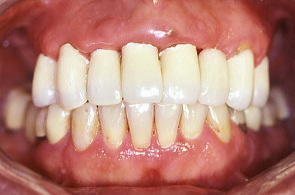

最初の写真は先にワックスで作った形を模倣して口腔内で再現し、仮り歯を作ったもの。次の写真は歯周外科を施し、深い歯周ポケットの歯垢を除去したところ。歯肉の色や艶が健康色を取り戻した。

矯正も兼ねて仮歯を修正:歯と歯の隙間を閉じる為仮り歯を修正したところ。患者は健康になり笑顔を取り戻した。日常の話やいろいろな悩みを聞いているうちに大分治療に慣れてきたように感じた。 そして物事をポジティブに考えられるようになってきたということだった。この頃から患者は体の調子を整える為、食事のダイエットを初めた。